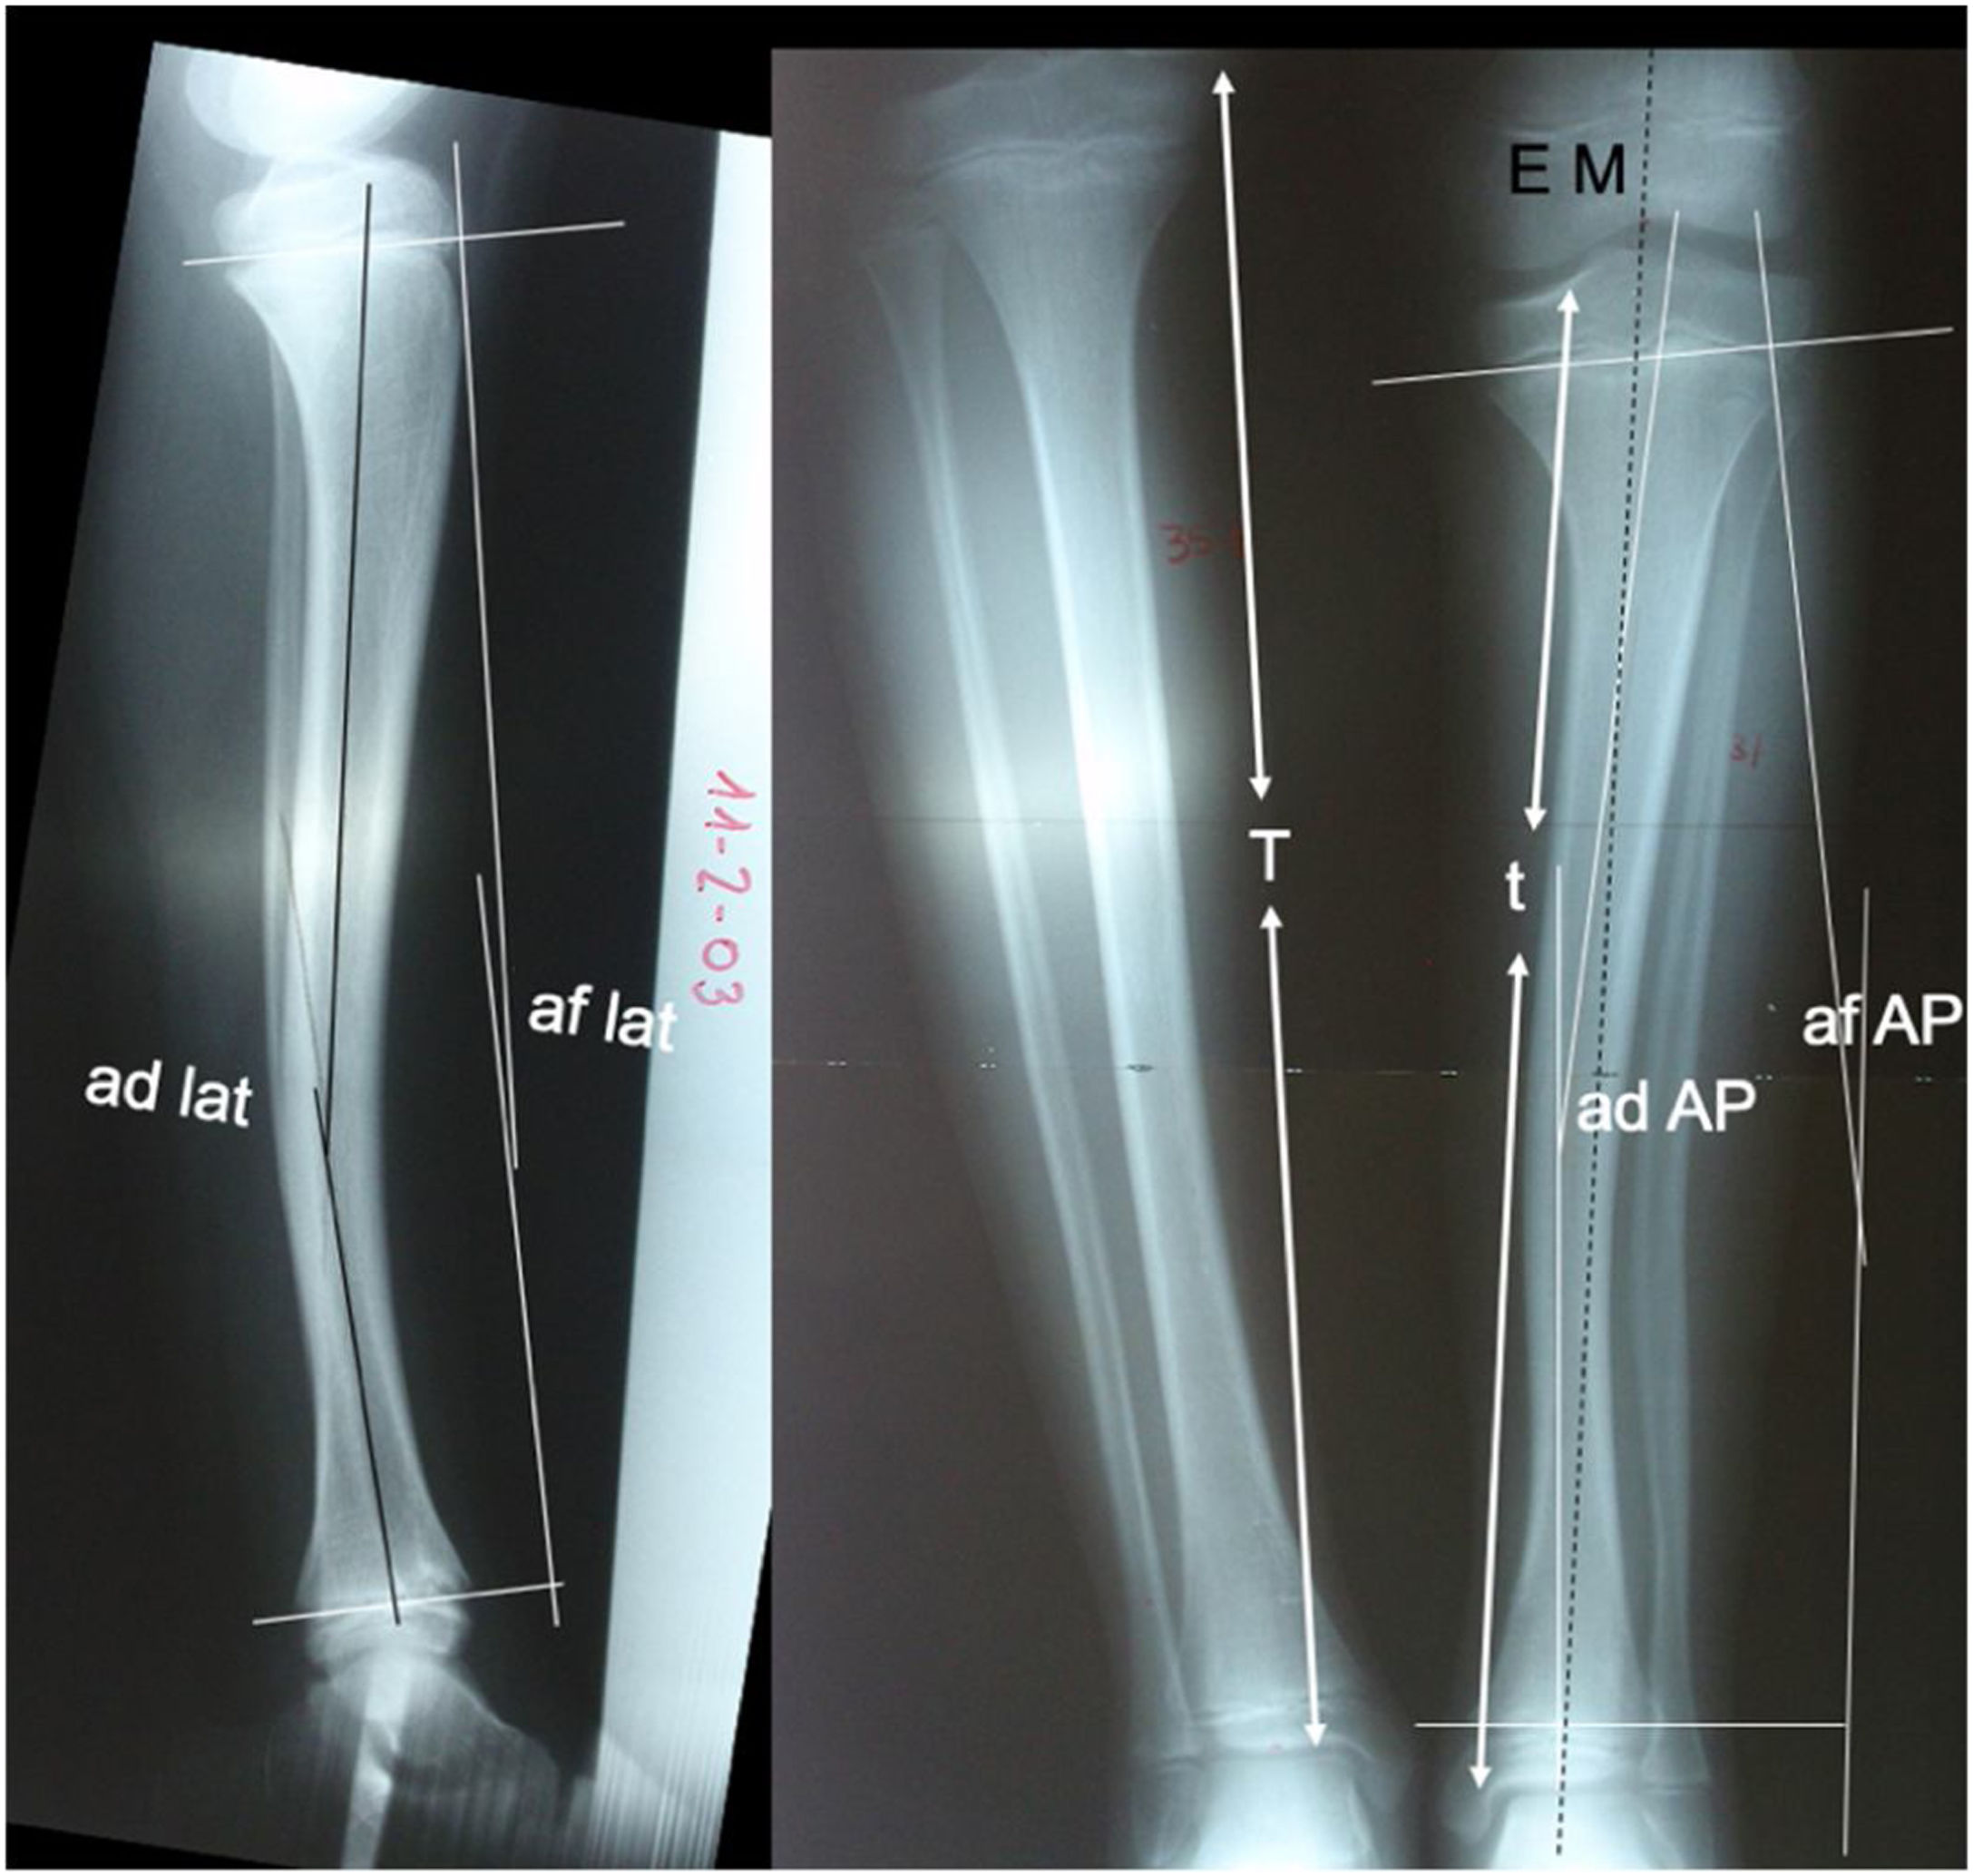

Se han registrado los datos radiológicos de los 14 casos estudiados: 1) Angulación diafisaria como la deformidad angular en los planos anteroposterior y lateral de la tibia afecta. 2) Angulación fisaria, medida como la relación angular de la fisis proximal con respecto a la distal en proyecciones anteroposterior y lateral y comparándolas con el lado contralateral sano. Estas mediciones se recogieron al nacimiento o primeros meses de vida, a los 5 y 12 años. Se valoró también la evolución del porcentaje de inhibición de crecimiento de la tibia afecta (t) con respecto a la tibia sana (T). La discrepancia de longitud de las extremidades se valoró realizándose la medición global y por segmentos anatómicos (fémures, tibia y el tarso observando la diferencia de altura de la interlínea tibio-astragalina) mediante tele-radiografía en proyección anteroposterior. Este mismo estudio radiológico se empleó para ver la evolución del eje mecánico del miembro afecto obteniéndose como puntos de referencia el centro de la cabeza femoral y el centro del astrágalo observándose la medialización o lateralización del eje a su paso por la rodilla y su recorrido por la diáfisis tibial (fig. 1).

ad AP: ángulo diafisario tibial en proyección anteroposterior; ad lat: ángulo diafisario tibial en proyección lateral; af AP: ángulo fisario en proyección anteroposterior; af lat: ángulo fisario en proyección lateral; EM: eje mecánico de la extremidad; T: longitud de la tibia sana; t: longitud de la DPMT.